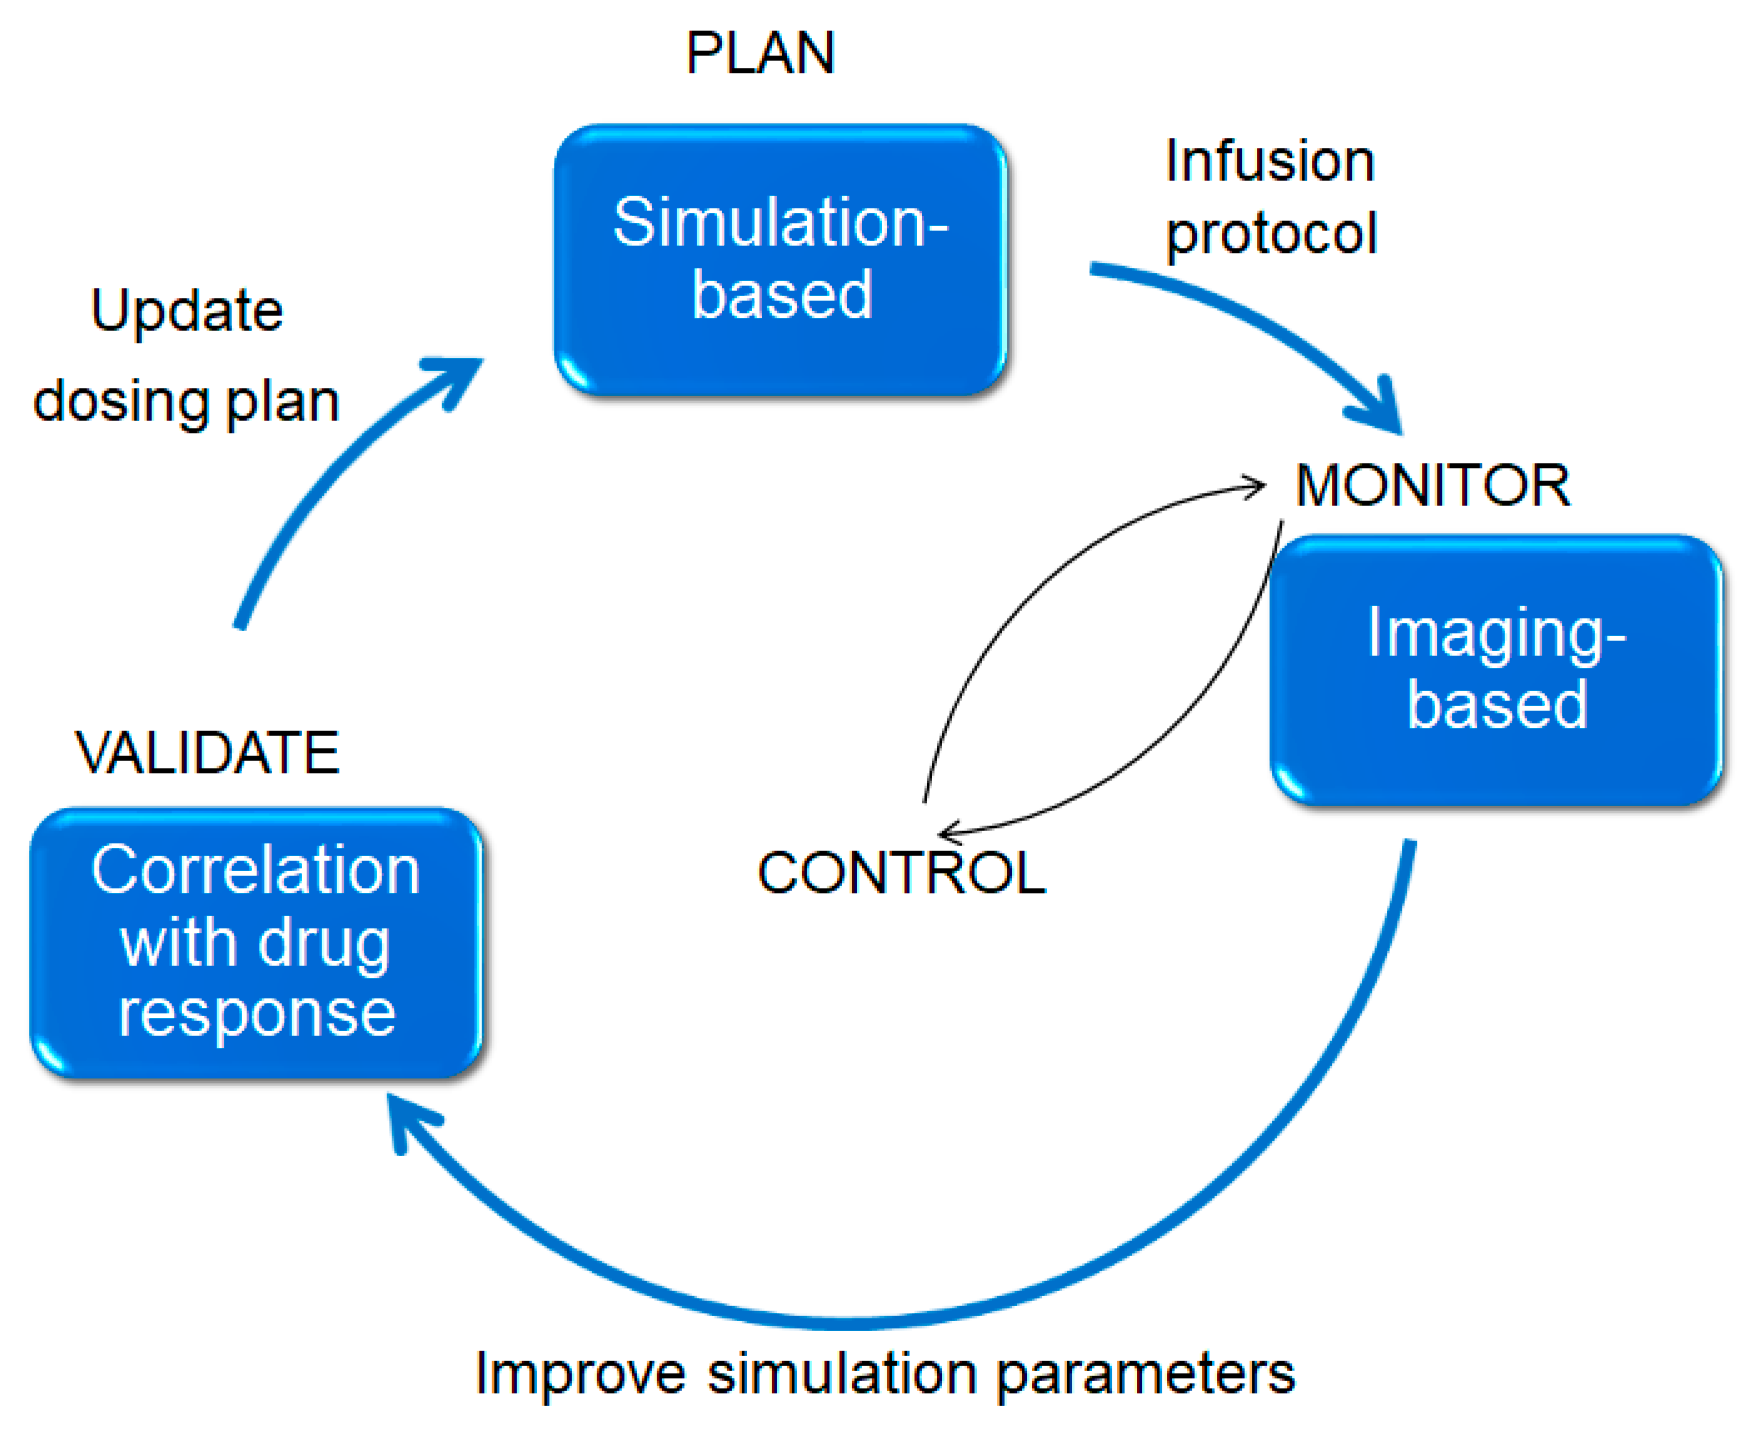

- Interstitium responses to infusion of fluid: Simulations and planning can reduce variability. Figure 18 illustrates an approach we hope to pursue and test in the future. An a priori plan (top) is used, in conjunction with neurosurgical expertise, to position the catheters to obtain best coverage of the target region. The infusion proceeds and a surrogate tracer is imaged (if conjugating the actual therapeutic particle with an imaging reagent is not possible).